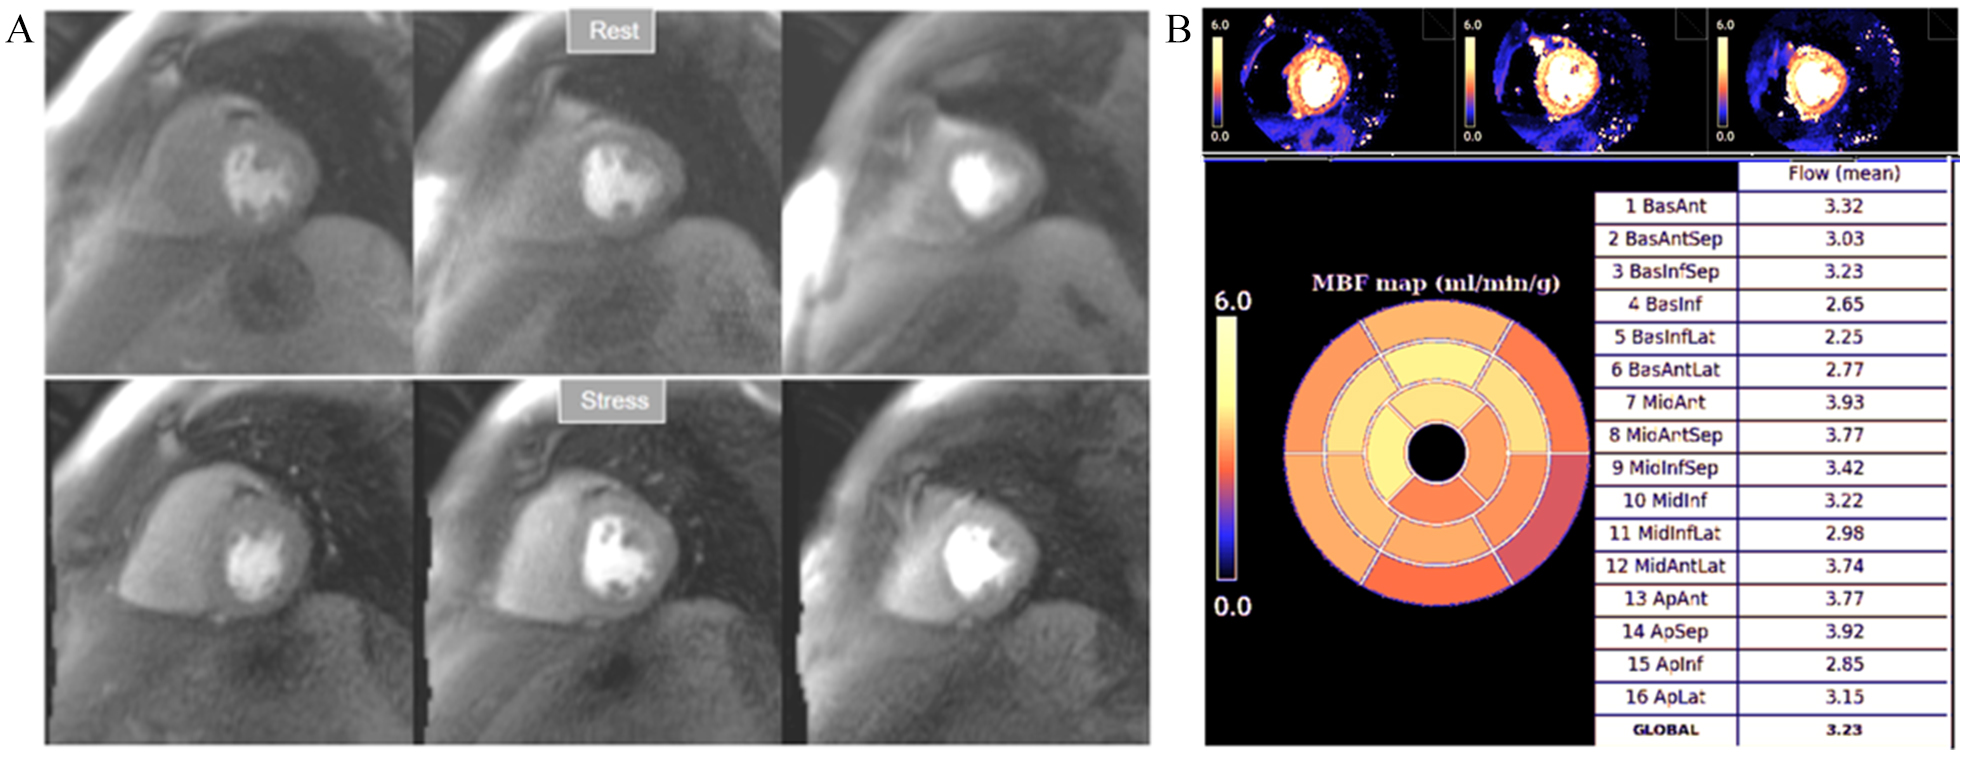

1.47 for the detection of significant obstructive lesions (

Fig. 32.Normal perfusion mapping. (A) Rest and stress perfusion studies showing absence of induced visual defect. (B) Normal global and segmental stress MBF.